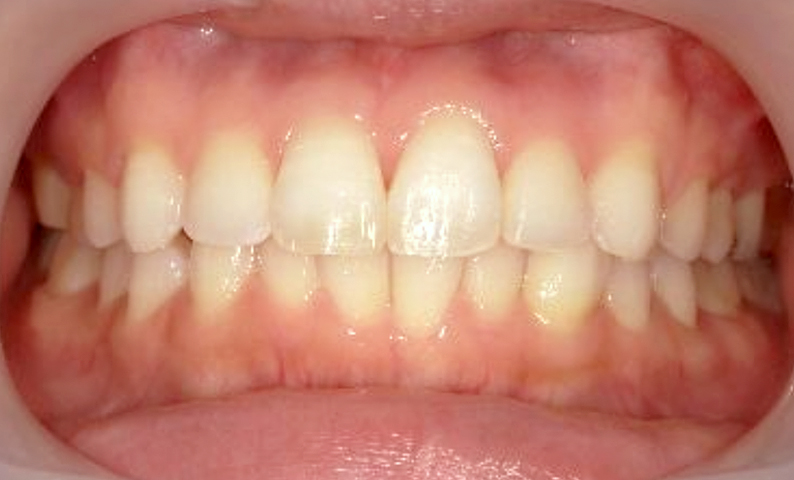

症例_025 上下顎の部分矯正

治療期間:13ヶ月金額:51万円+税女性前歯のガタガタ出っ歯

| Before | After |

|---|---|